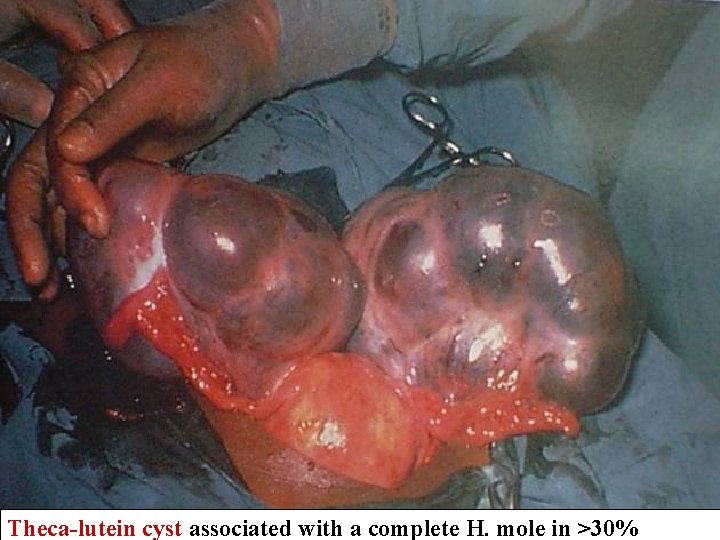

Complete H. Mole Microscopically Enlarged, edematous villi and abnormal trophoblastic proliferation that diffusely involve the entire villi No fetal tissue, RBCs or amnion are produced Macroscopically, these microscopic changes transform the chorionic villi into clusters of vesicles with variable dimensions “ like bunch of grapes" No fetal or embryonic tissue are produced Uterine enlargement in excess of gestational age. Theca-lutein cyst associated in 30%

Complete H. Mole with large for date uterus& Theca-lutein cyst Patient was 42 years 5 th G P 5 initial Bh. CG: 195, 000 m. IU/m. L Complete H. Mole After Hysterectomy

Theca-lutein cyst associated with a complete H. mole in >30%